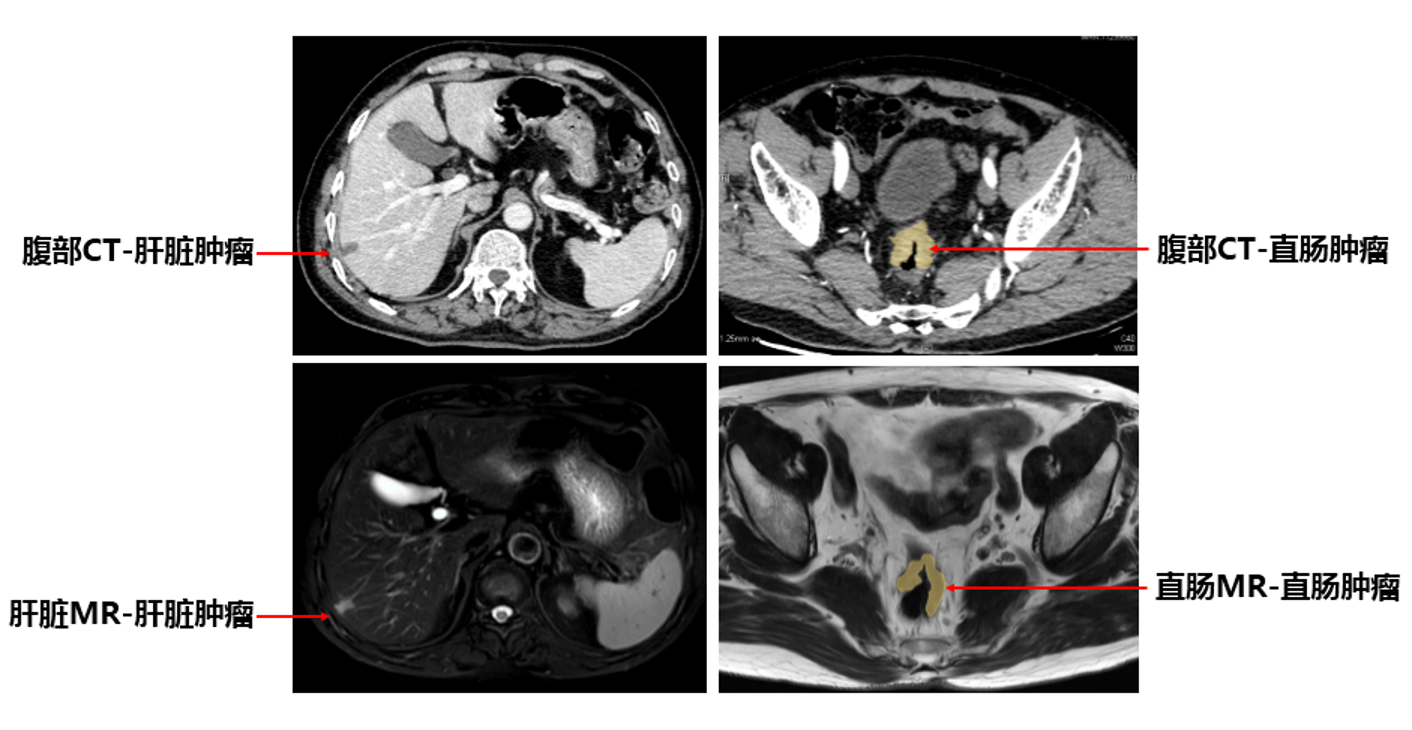

患者影像

患者为58岁男性,因近3个月反复便血来到我院胃肠外科李元新门诊,肠镜检查提示距肛门9-12cm处存在环半周溃疡型肿物,大小约3*4cm,病理为腺癌,进一步全腹部增强CT与核磁提示直肠恶性肿瘤,并怀疑伴有肝转移。“原发肿瘤位于直肠中段,侵出肠壁肌层,由于区域淋巴结无肿大,环周切缘与壁外血管侵犯阴性,肿瘤复发风险较小,不需要进行放疗。”李元新说,“这种情况,我们采用高质量的全直肠系膜切除手术(TME),对患者获益较大。”